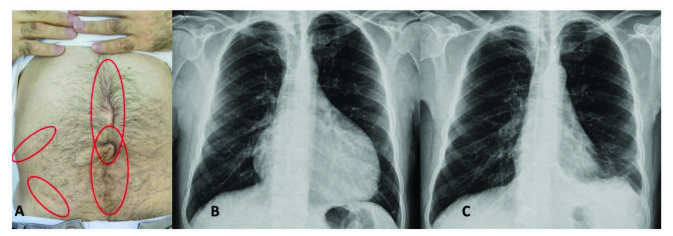

腹膜发作开始局限并迅速蔓延至整个腹部。腹膜炎症会导致典型的肠梗阻症状,患者会遭受严重的胃痛。体格检查显示腹部肌肉僵硬、反跳痛和肠鸣音消失——临床上这种紧急情况与急腹症的手术原因无法区分。因此,隐匿性腹部手术史在良性阵发性腹膜炎患者中很常见(图 1A)。在疑似病例中,影像学检查可能有助于排除手术病理。腹部发作后可能会出现轻度反弹性腹泻。尽管有戏剧性的表现,但腹膜炎的所有体征和症状在 24-72 小时内完全消退,没有后遗症,尽管慢性腹水和腹膜粘连的报道很少。

图1:(A) 一位因多次腹部手术而留下疤痕的患者,(B) 胸部 X 光片显示大量心包积液,(C) 同一患者用阿那白滞素治疗后的胸部 X 光片。

不到 50% 的患者会出现胸膜炎发作,表现为突然发作的单侧胸膜炎,可能单独发生,也可能与腹膜炎和发热同时发生。患者描述了典型的严重胸膜炎性胸痛,经检查,他们的胸部患侧呼吸音减弱。胸部 X 光片可能显示肋膈角有少量渗出液。发作通常会在一到三天内完全消退。

心包炎是一种罕见病症,见于 1%–2% 的患者。心包炎会出现胸骨后胸痛和呼吸困难等症状。心包填塞可能很少发生。心电图显示 ST 段抬高,胸部 X 光片可能显示心脏轮廓的短暂扩大(图 1B 和 1C),超声心动图显示心包积液。在极少数情况下,复发性心包炎可能是良性阵发性腹膜炎的唯一表现,这可能与特发性心包炎相混淆 。